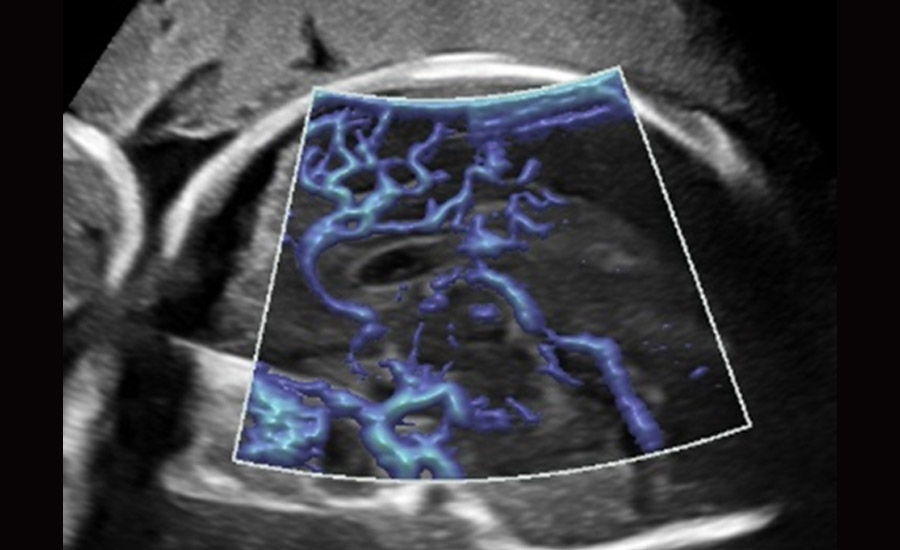

UMA (Ultra-Micro Angiography)

The innovative technology breaks the bottlenecks of traditional Doppler imaging. With ultra-high spatial resolution and flow sensitivity, it allows detecting super-subtle and super-slow flow perfusions, thereby extending the clinical application of qualitative and quantitative ultrasound evaluation in fetal brain, kidney, placenta, endometrium, ovary, etc.

3D UMA - fetus intracranial flow

3D UMA - perifollicular blood flow